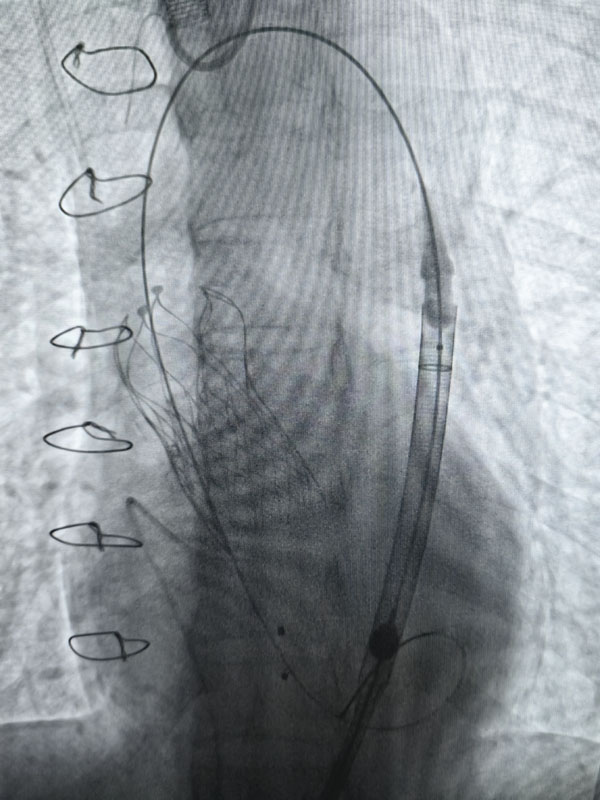

經(jīng)過充分的術前準備,兩臺手術由心血管外科趙永波副主任主刀,趙偉超主治醫(yī)師、侯五輝主治醫(yī)師密切配合,選擇經(jīng)皮股動脈穿刺,預埋縫合器,術中反復造影,準確定位釋放瓣膜,術后造影及超聲提示人工瓣膜開啟功能良好。為確保術中安全,體外循環(huán)小組全程保駕護航。患者生命體征平穩(wěn),術后一日均轉出監(jiān)護室。